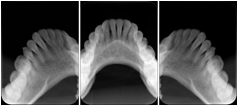

2 Occlusal Vertical Maxilla A Dental Image Layout

DL-C001A

Reference: DL-C001-U1L0

Reference: DL-C001-U2L0

00

Occlusal

18, 17, 16, 15, 14, 13, 12, 11, 13, 12, 11

01

21, 22, 23, 24, 25, 26,27, 28

2 Occlusal Vertical Mandible A Dental Image Layout

DL-C002A

Reference: DL-C002-U0L1

Reference: DL-C002A-U0L2

10

48, 48, 47, 46, 45, 44, 43, 42, 41

11

31, 32, 33, 34, 35, 36, 37, 38

2 Occlusal Horizontal Maxilla A Dental Image Layout

DL-C003A